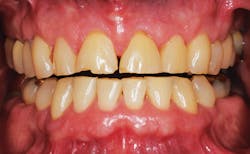

Figure 3: Attrition indicative of bruxism.

Tooth wear is a process resulting from three primary factors-abrasion (from the interaction of teeth with other materials); attrition (from tooth-to-tooth contact); and erosion (wear after teeth come into contact with environmental or dietary acids) (see Figures 2-5). In addition, numerous behaviors and health factors contribute to the process of tooth wear, including, but not limited to: a diet high in acidic beverages and foods, bruxism, aggressive or improper tooth brushing, low pH of the oral cavity (acid reflux, GI disorders, bulimia nervosa) and oral hygiene habits.